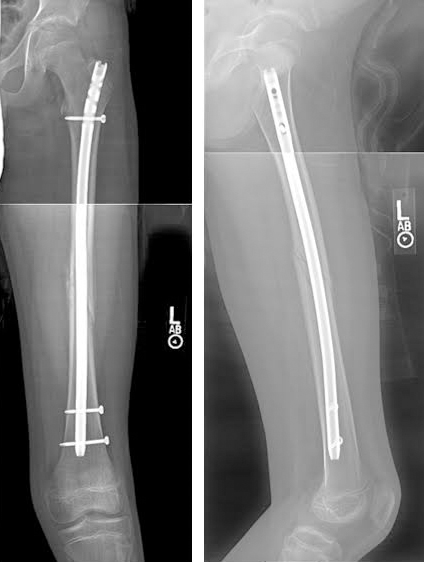

• What are the implants we use for fracture fixation?

Implants are made from metal most commomly stainless steel or titanium. Depending on the fracture configuration and the bone we use

• Nails or Rods